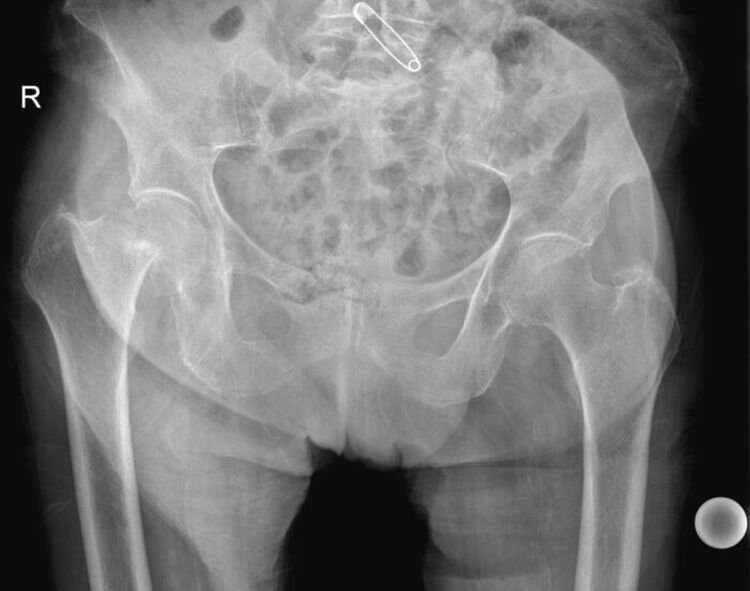

Διατροχαντήριο κάταγμα οστεοσύνθεση με ήλο

74χρονη ασθενής είχε μια πτώση όπως έβγαινε από το αυτοκίνητο. Κατά την πτώση υπέστηενα διατροχαντήριο κάταγμα του δεξιού μηριαίου. Διακομίστηκε στο τμήμα επειγόντων περιστατικών όπου και διαπιστώθηκε το κάταγμα μετά από

Διαβάστε περισσότερα